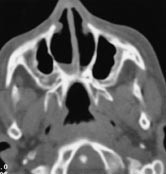

Diagnosen koanalatresi stilles gjerne ved sondering og bekreftes ved CT-bilder. Tette snitt i området nese-epipharynx gir god anatomisk kartlegging og avklarer også om andre lokale skjelettdeformiteter er til stede. Figur 1 viser anatomien ved ensidig koanalatresi. Figur 2 viser et CT-bilde ved dobbeltsidig koanalatresi.

Operasjonsmetodene er forskjellige. Noen nøyer seg med å perforere atresien og så dilatere den (8, 9). De fleste utvider den ved å fjerne det atretiske vev med bor eller stanse (2, 3, 5, 10, 11). Noen bestreber seg på å bevare slimhinnelapper, men det er svært vanskelig hos spedbarn. Laser benyttes iblant for å åpne atresien (12), men metoden har sine begrensninger (13). Best varig effekt oppnås ved at man i tillegg fjerner noen millimeter av bakre ende av vomer (3, 5). Ut fra anatomiske betraktninger (fig 1, 2) synes det hensiktsmessig, og vi har fått bedre resultater etter at vi begynte med det. Perforasjon og dilatasjon alene var ikke effektivt. For å hindre residiv må åpningen holdes åpen med en form for tamponade til såret er tilhelet. Vanligvis brukes silikonrør. Freng fikk gode resultater med å la drenene stå inne i seks uker (2). Det er ingen enighet om hvor lenge de bør stå inne. Jung benyttet seks dager (10), mens de fleste lar dem stå i 8 – 16 uker (6, 8, 14). Vi har latt dem stå i 12 uker. Så lenge de er på plass, går respirasjonen gjennom nesen uhindret. Tykkelsen på rørene er avgjørende for resultatet. Hvis de er for tykke, klemmes de sammen, nesepustingen hindres samtidig som rørene trykker mot omkringliggende vev og hindrer sårtilheling, og det disponerer for residiv.